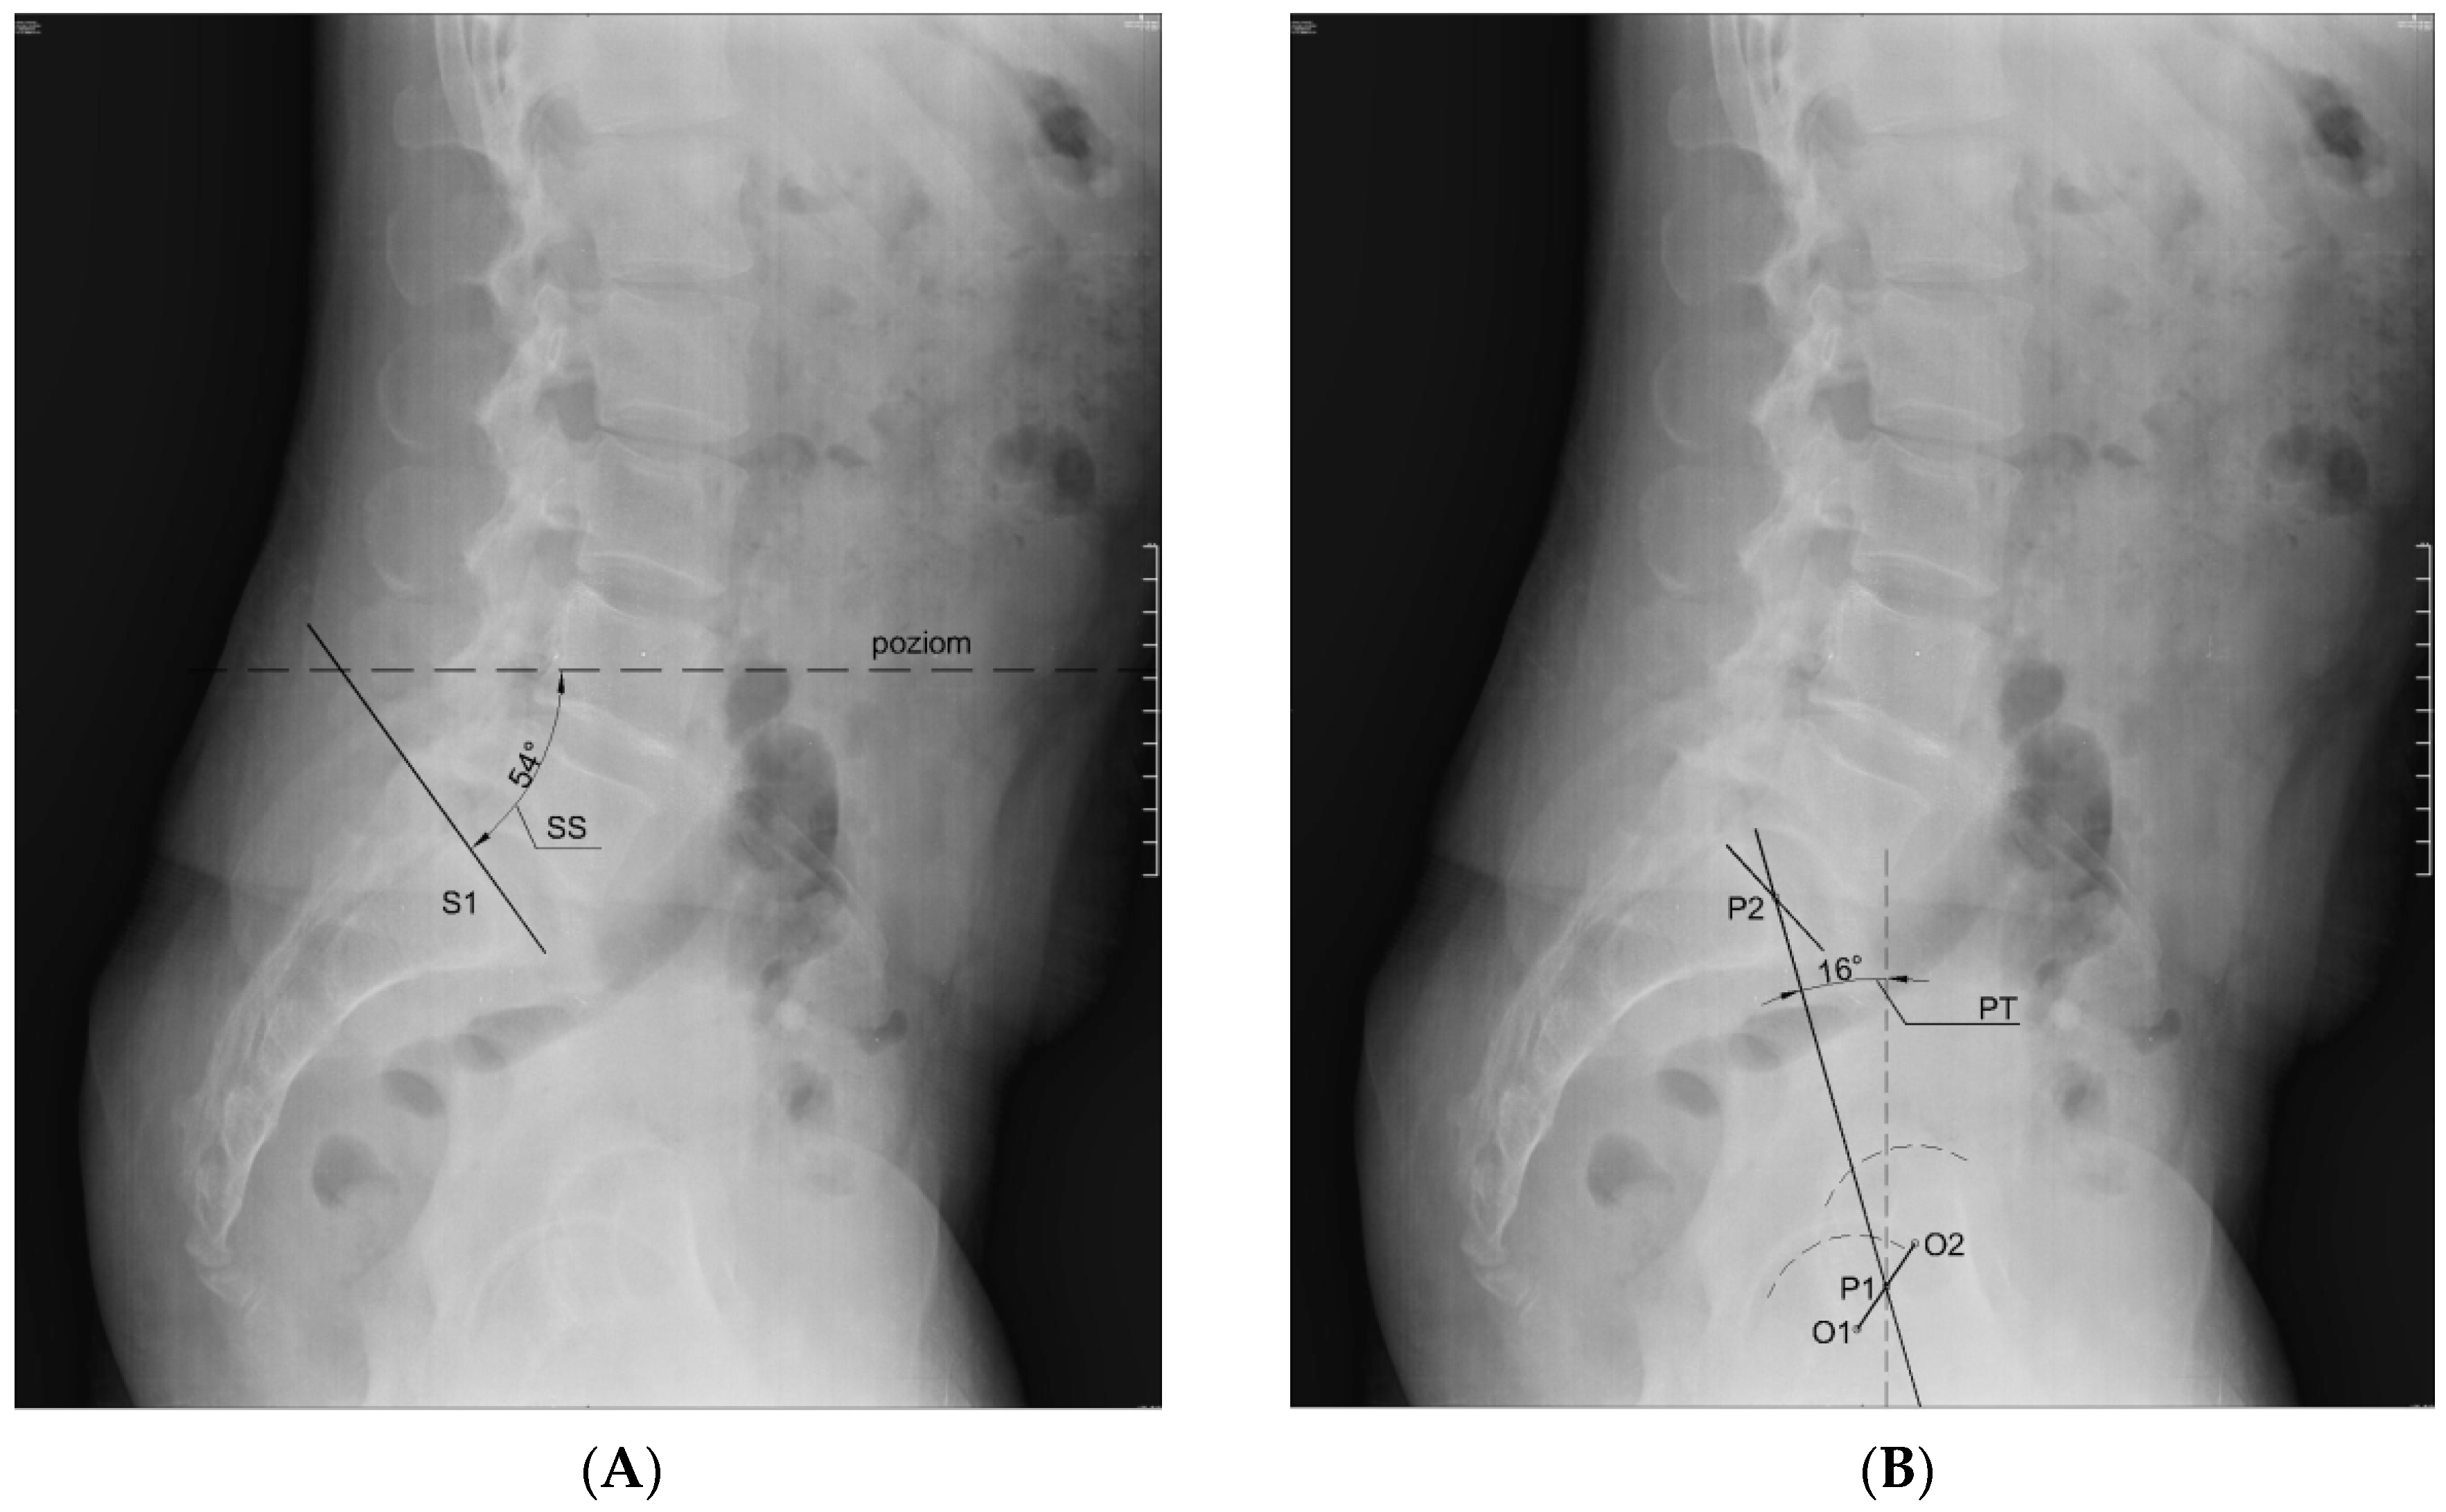

The mobility range test of the knee joints was performed first (goniometer MoVes 08-030202). The results of the test determined whether or not the candidate was included in the study. Secondly, body weight and height were measured (portable height meter Leicester Tanita HR 001, Tanita; weight measuring device Tanita BC-543, Tanita), and the BMI was calculated. In the next step, the researchers performed an X-ray in the lateral projection in standing position with the visualization of the lumbar spine, the pelvis, and the femoral heads. The subjects were asked to take a relaxed stance with their hands crossed on their chest (fists on the clavicles). If the flexion contracture occurred on the right side, the subjects were asked to position themselves with their right side to the radiation source, and if the flexion contracture occurred on the left side, they were asked to position themselves with their left side to the source of the radiation. The subjects kept their footwear for the X-ray test. If the subjects wore shoe inlays on a daily basis, the X-ray was done with them. The distance from the radiation source was 100 cm. The radiation beam was targeted at the L3 vertebra. Measurement of the angle values of indicators characterizing the position of the lumbar–pelvic complex—SS, PT, PI, and LL (Figure 1)—was established on the basis of X-ray imaging analysis. Measurements were made using AutoCAD LT 2013 software (Autodesk). The correctness of plotted angles was assessed by radiologist (MS) using the mediCAD program (mediCAD Hectec GmbH).

Figure 1. Method of plotting of the angle denoting: A—the sacral slope (SS) in the sagittal plane; B—the pelvic tilt (PT) in the sagittal plane; C—the pelvic incidence (PI) in the sagittal plane; D—the value of curvature of the lumbar spine (lumbar lordosis, LL) in the sagittal plane. Source: archive of own images.